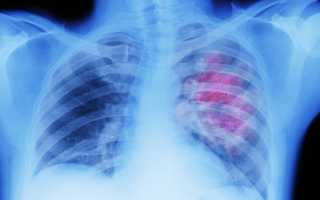

Диагностика

Для того чтобы верно определить причину скопления жидкости и назначить лечение, врачу необходимо провести диагностику. Обследование больного проходит в несколько этапов. Сначала изучают оба легких пациента путем:

- визуализации грудной клетки — при некоторых формах болезни меняется и форма грудины;

- определения болевых точек;

- ультразвукового исследования;

- лабораторного исследования выпота.

Информация! Кроме этого, назначают исследование крови, в котором определяют количество газов в составе биоматериала, наличие раковой опухоли и свертываемость.